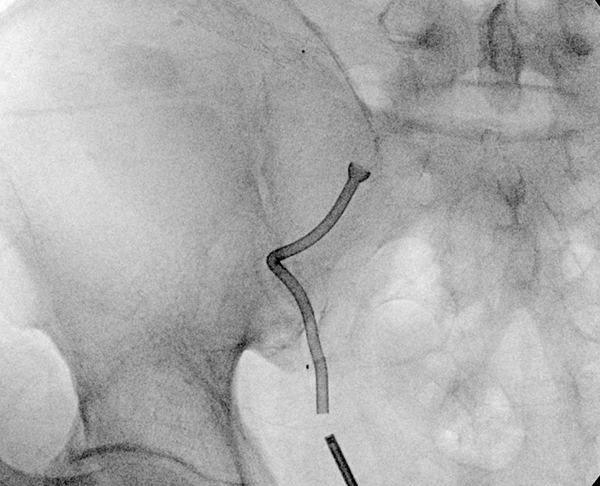

▲图示:移植肾输尿管温控支架位置良好

在泌尿外科首席专家谷现恩和龙建华的带领下,团队对彭先生的病情进行了系统评估和深入分析,并制定了详尽的治疗方案。此次手术,应用了国产温控支架来治疗移植肾输尿管狭窄,这在医院尚属首例。该支架具备长期留置的特性,有效减少了患者频繁更换支架的痛苦与不便,为移植肾输尿管狭窄的治疗开辟了新路径。国产温控支架的成功应用不仅是医疗器械研发领域的创新成果,也为患者提供了更经济、更高效的治疗选择。这一技术的突破彰显了国产医疗设备在复杂病症治疗中的强大实力。